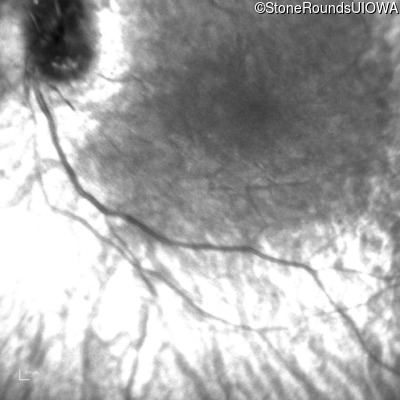

Infrared Fundus Photograph - Right -

No Light Perception

Exemplar

Expanded OCT Stack

×